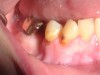

Fig 1. Radiographs showing an example of “meth mouth.”

Figure 1